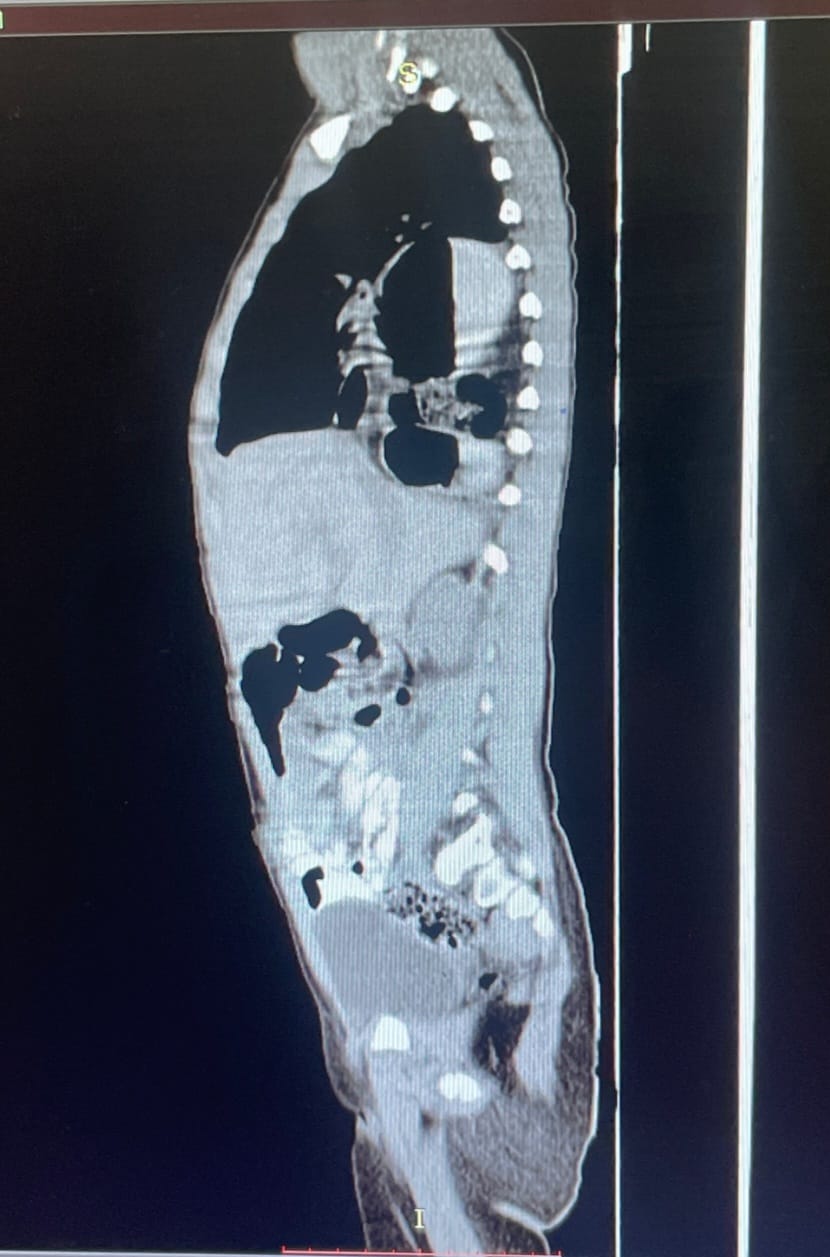

Uşağı bu vəziyyətə salan səbəb diafraqmada olan böyük defektdən mədənin və bağırsaqların döş qəfəsinə keçməsi (Paraözofagial diafraqma yırtığı) olub.

Çəkisi cəmi 13 kq olan uşağa Paraözofagial yırtığın təmiri və Nissen fundoplikasiyası əməliyyatını uğurla icra edilib.

Döş boşluğuna keçən mədə, nazik və yoğun bağırsaqların böyük qismi qarın boşluğuna qaytarılaraq diafraqmadakı defekt bərpa edilib.